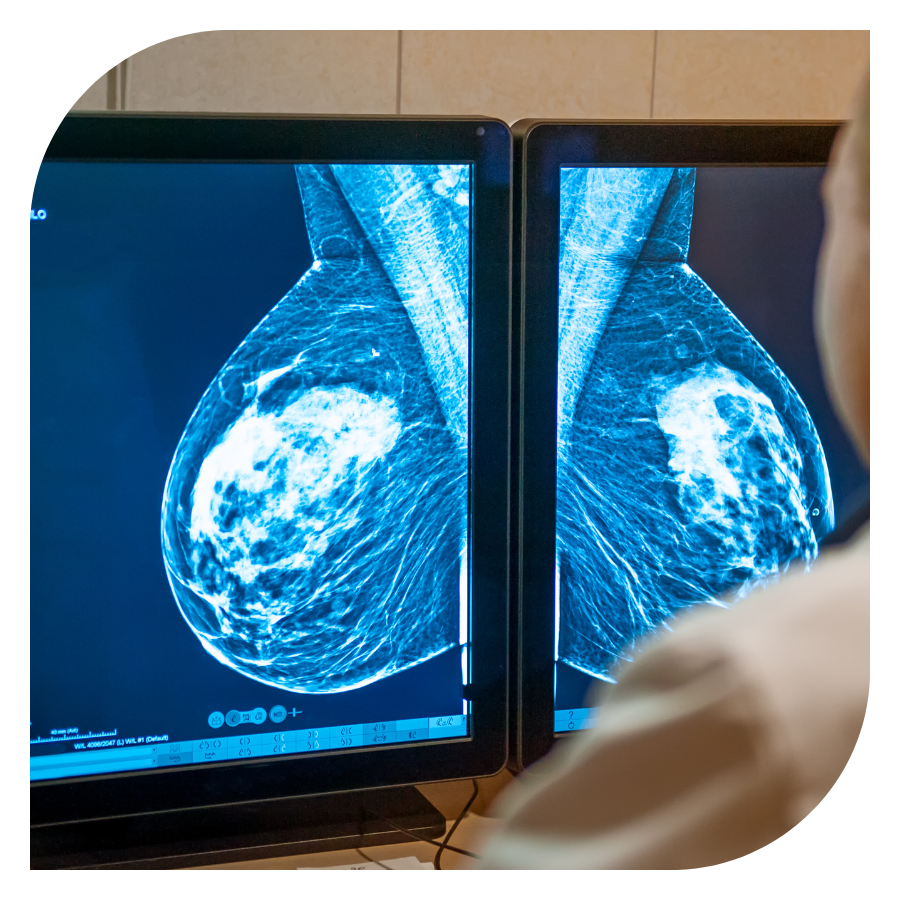

Para podermos diagnosticar o tumor ainda na fase inicial, curável, precisamos fazer exames de rotina, preventivos. Por isso, a partir de 40 anos, o ideal é que anualmente a mulher faça seus exames de screening, especialmente a mamografia.

O diagnóstico do câncer de mama se dá pela combinação de exame físico pelo médico, exames de imagem e a biópsia mamária. Ao suspeitar de um nódulo mamário ou em exames rotineiros o médico solicita mamografia, ultrassom de mamas e/ou ressonância de mamas. Se o exame demonstra lesão suspeita, o médico deverá solicitar uma biópsia do nódulo. A patologia (resultado da biópsia) é o padrão ouro do diagnóstico de câncer.